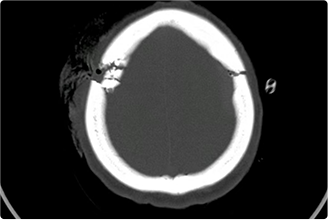

神經(jīng)創(chuàng)傷與重癥中心主要是針對神經(jīng)系統(tǒng)疾病的急危重癥患者進行全面地救治,涉及顱腦創(chuàng)傷以及出血的各種常規(guī)開顱、顯微/內(nèi)鏡下顱底修復(fù)與重建、復(fù)合手術(shù)、復(fù)雜的腦積水和顱面骨缺損修復(fù)成形手術(shù)、綜合治療神經(jīng)系統(tǒng)感染等。

擅長腦血管病(出血與缺血)的神經(jīng)介入與微創(chuàng)手術(shù),能熟練開展腦外傷、重度顱腦損傷的救治工作。